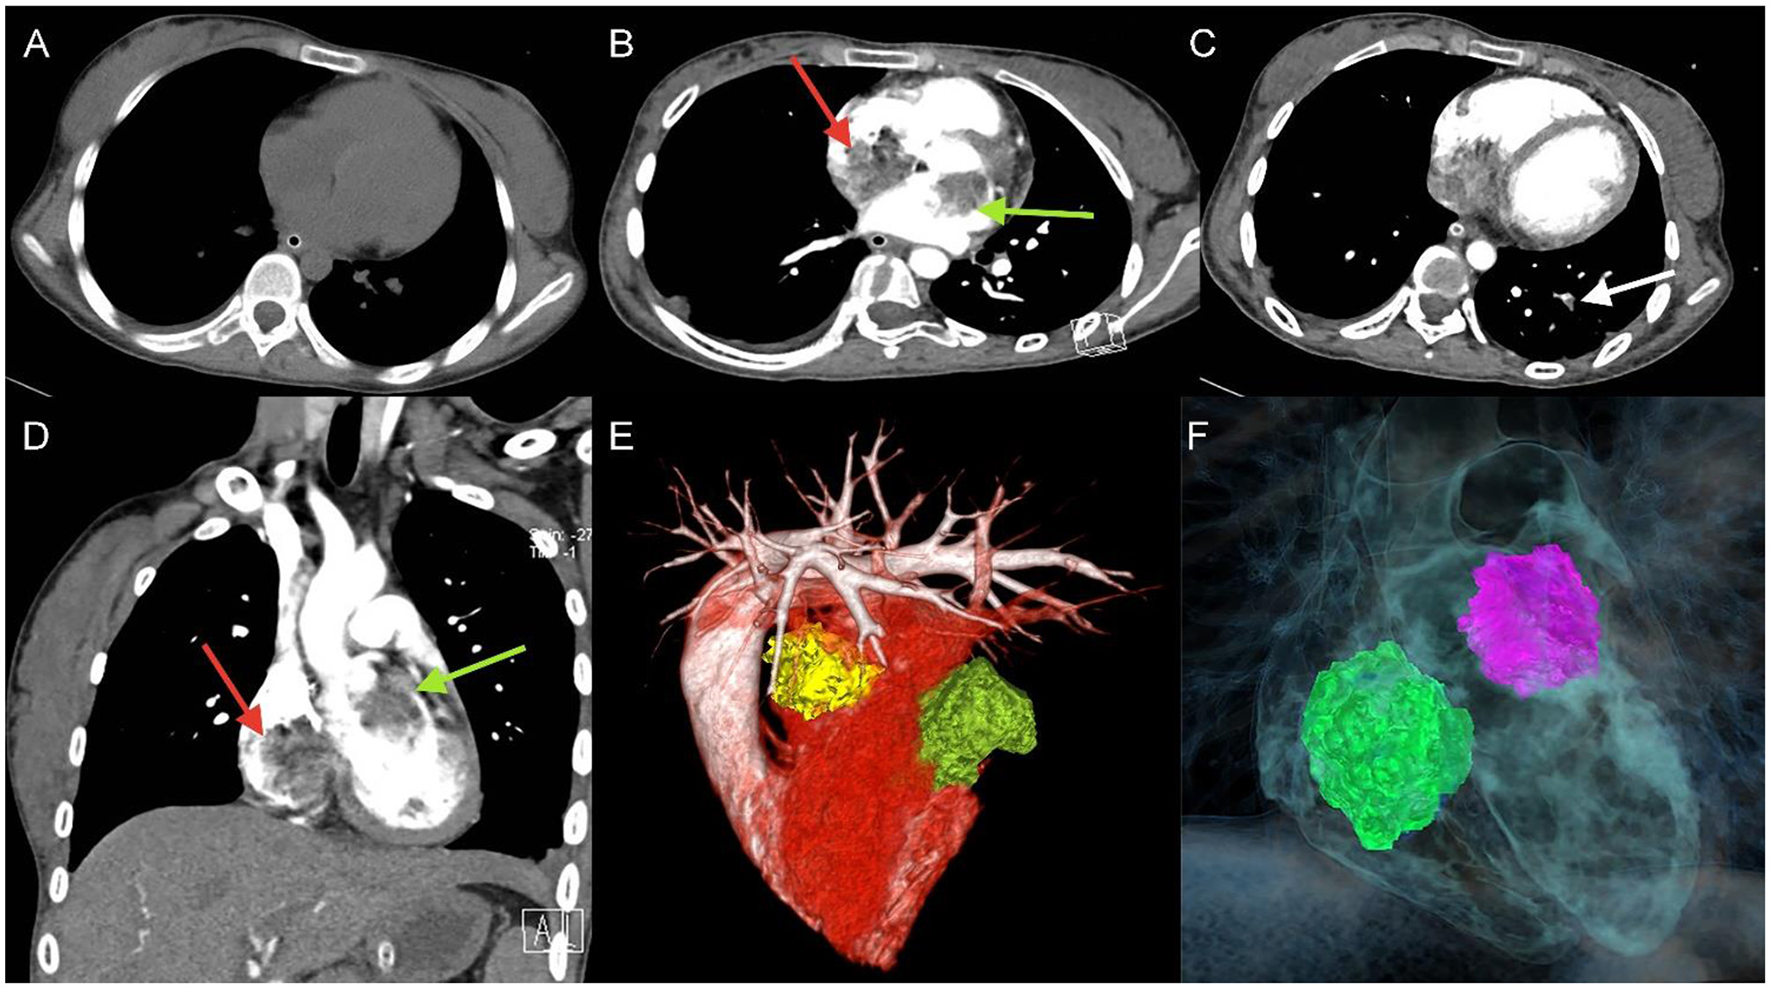

Figure 1

Unenhanced thoracic CT (A), axial and coronal views of Computed tomography pulmonary angiography (CTPA) detected filling defects in right atrium (red arrow), left atrium (green arrow) (B,D), and left lower pulmonary basilar artery (white arrow) (C), three-dimensional reconstruction of heart (E) and (F) corresponding schematic illustration demonstrating the biatrial myxoma.

A 17-year-old girl presented to our hospital on August 22, 2021 with clouding of consciousness for more than 3 days. At 3+days prior, the patient was unable to speak the patient was unable to speak when called softly and unable to open the right eye, combined with involuntary movements of the limbs and incontinence. The patient visited the local hospital immediately, where relevant tests were performed, suggesting intracranial lesions. Since the specific treatment measures were unavailable at the previous hospital, she was transferred to our hospital for further treatment. There was no history of trauma or familial genetic diseases, such as high blood pressure and diabetes. Physical examination revealed a body temperature of 37.0°C, heart rate of 110 bpm, regular heart rhythm, blood pressure of 113/77 mmHg, and no pathological murmurs in the valve region; pulmonary auscultation revealed coarse rales in the entire lung. The pupils were equal, round, and pupillary light reflexes were delayed. Both lower limbs exhibited hypertonia and hyperreflexia of the knee and tendon reflexes. Laboratory examinations revealed the following levels (normal range): coagulation function test showed D-dimer was 0.57 mg/L (< 0.5 mg/L) and fibrinogen was 5.82 g/L (2.00–4.00 g/L). Routine blood tests showed that the absolute value of neutrophils was 7.38 × 109/L (1.8 × 109/L−6.3 × 109/L). Infection-related markers showed that the hypersensitive C-reactive protein level was 111.563 mg/L (0.068–8.200 mg/L). Creatine kinase, α-hydroxybutyrate dehydrogenase, and lactate dehydrogenase levels were 148 U/L (26–140 U/L), 218 U/L (90–180 U/L), and 295 U/L (140–271 U/L), respectively. Computed tomography pulmonary angiography (CTPA) detected filling defects in the right atrium, left atrium, and left lower pulmonary basilar artery (Figure 1), and a diagnosis of Pulmonary embolism was made. Transthoracic echocardiography (TTE) revealed irregular iso-echoic masses in the bilateral atrium that were likely myxomas, given their location and appearance in a young patient; the myxoma in the left atrium measured approximately 38 × 21 mm, and it was attached to the junction of the lower part of the interatrial septum (IAS) and the root of the anterior mitral leaflet; in the right atrium it measured approximately 51 × 27 mm, and it was attached to the lower part of the IAS (Figure 2A). These masses resulted in the acceleration of the tricuspid valve antegrade flow (Figure 2B). Craniocerebral computed tomography (CT) showed extensive hypodensity in the bilateral parts of the pons and patchy hypodensity in the left corona radiata area and bilateral basal ganglia areas. Magnetic resonance imaging (MRI) also revealed extensive hypointensity on T1-weighted imaging and hyperintensity on T2-weighted imaging in the bilateral parts of the pons, and a patchy hyperintensity on T2-weighted imaging in the bilateral basal ganglia areas; bilateral centrum semiovale; and right frontoparietal lobe, which presented as high signal on diffusion-weighted imaging (DWI) (Figure 3). This confirmed the diagnosis of brain ischemia. To prevent thrombosis, low molecular weight heparin calcium (subcutaneous injection, 0.4 ml/12 h) was commenced on the second day of admission and continued until discharge. The patient underwent successful removal surgery for a biatrial myxoma. The masses were sent for histological examination, which confirmed the presence of a myxomatous matrix containing myxoma cells (Figure 4). The patient recovered uneventfully and was discharged 9 days after the procedure. The patient has been followed-up postoperatively for over 2.5 months, and limb motor function of the patient has recovered to some degree, but there is intellectual and cognitive decline.

Pulmonary embolic events are rare, but when they occur, it is important to identify the source of the embolus, and in previous reviews of the literature, the majority of emboli originated from deep venous thrombosis (DVT), accounting for about 50–70%. In addition to DVT, cancer-related emboli are also quite common (19). Clinically significant embolic events are uncommon in patients with atrial myxoma. However, in cases of right atrial or right ventricular myxoma, embolectomy of tumor fragments into the pulmonary vasculature with subsequent pulmonary hypertension has been reported (14). In the early stages of pulmonary embolism, the clinical symptoms and imaging manifestations are atypical, and it is easy to misdiagnose pulmonary embolism as pneumonia; however, the role of non-contrast chest CT scans in the diagnosis of pulmonary embolism is limited; currently, the preferred technique for the diagnosis of pulmonary embolism is CTPA, which can detect filling defects in the pulmonary circulation and help to confirm the diagnosis of pulmonary embolism, and it is clinically important to assess the severity of a patient's pulmonary embolism based on the results of CTPA (20). In our case, infiltrates were seen in the posterior basal segment of the left lower lung lobe on non-contrast chest CT and the patient was diagnosed with pneumonia; subsequent CTPA clearly showed the infiltrates to be filling defects of the pulmonary artery.

Imaging such as CT, MRI, TTE, and CTPA play an important role in the preoperative diagnosis of cardiac myxoma. Transthoracic echocardiography can reveal the location of the tumor attachment and the appearance features of the mass. Computed tomography pulmonary angiography is a useful tool that shows the location, size, and appearance of pulmonary emboli. Imaging approaches can play a key role in the diagnosis of symptomatic or asymptomatic cases. We recommend non-invasive imaging examinations for preoperative diagnosis of patients with cardiac myxoma. According to the results of these examinations, the patients underwent surgery and the mass was totally resected, and their operation was successful.